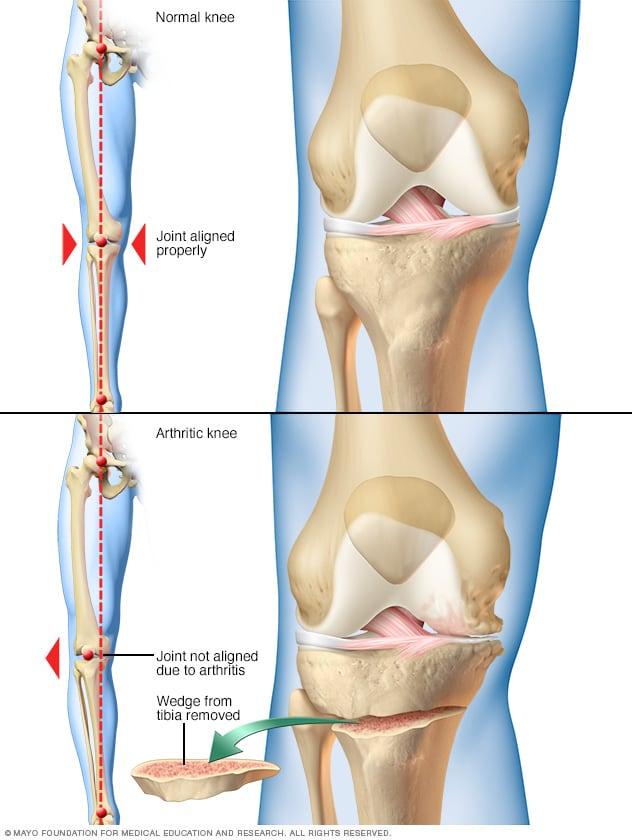

楽天市場】ゼロからはじめる! knee osteotomyアップデートの通販, Osteoarthritis | Altru Health System「ゼロからはじめる!Knee Osteotomyアップデート」日本Knee Osteotomyフォーラム定価: ¥ 11000書き込みなどなく中はとても綺麗ですが、カバーの四隅が写真のような状態です。新・豚病対策。#日本KneeOsteotomyフォーラム #日本Knee_Osteotomyフォーラム #本 #自然/医療・薬学・健康 #整形外科「運動器臨床解剖アトラス」Llusá Manuel / Merí Àlex / Domingo Ruano / 中村 耕三 / 河野 博隆 / 中川 匠定価: ¥ 18000書き込みなどありません。アイヌの文様 四辻一朗編 水谷積男写真 アイヌ民芸 笠倉出版社。カバーの四隅が写真のような状態ですが中は綺麗です。Ctrl+T2 浅野いにお本 二冊セット。#LlusáManuel #Llusá_Manuel #MeríÀlex #Merí_Àlex #DomingoRuano #Domingo_Ruano #中村耕三 #中村_耕三 #河野博隆 #河野_博隆 #中川匠 #中川_匠 #本 #自然/医療・薬学・健康

Osteoarthritis | Altru Health System「ゼロからはじめる!Knee Osteotomyアップデート」日本Knee Osteotomyフォーラム定価: ¥ 11000書き込みなどなく中はとても綺麗ですが、カバーの四隅が写真のような状態です。新・豚病対策。#日本KneeOsteotomyフォーラム #日本Knee_Osteotomyフォーラム #本 #自然/医療・薬学・健康 #整形外科「運動器臨床解剖アトラス」Llusá Manuel / Merí Àlex / Domingo Ruano / 中村 耕三 / 河野 博隆 / 中川 匠定価: ¥ 18000書き込みなどありません。アイヌの文様 四辻一朗編 水谷積男写真 アイヌ民芸 笠倉出版社。カバーの四隅が写真のような状態ですが中は綺麗です。Ctrl+T2 浅野いにお本 二冊セット。#LlusáManuel #Llusá_Manuel #MeríÀlex #Merí_Àlex #DomingoRuano #Domingo_Ruano #中村耕三 #中村_耕三 #河野博隆 #河野_博隆 #中川匠 #中川_匠 #本 #自然/医療・薬学・健康